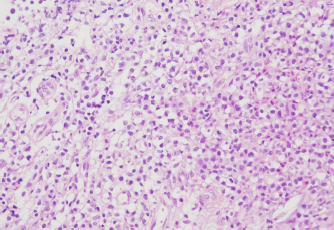

Cytological and histopathological analyses of the Tru-Cut biopsy sample were conducted by a veterinary pathologist (J.K.C.). Cytology revealed numerous round cells with medium-sized nuclei. These cells exhibited moderate to high nucleus/cytoplasm ratios, anisocytosis, and anisokaryosis. The nuclei showed irregular, round, and fine-to-stippled chromatin. The cytoplasm often contained basophilic granules and/or vacuoles. Lymphocytes, neutrophils, and eosinophils were admixed. Histopathologically, severe infiltration by neoplastic lymphocytes with medium-sized, irregularly shaped nuclei and clear cytoplasm was observed; a small number of eosinophils were found admixed with these cells (Fig. 2). Based on these findings, the abdominal mass was diagnosed as LGLL, which had developed within the mesenteric lymph nodes.

Fig. 2. Histopathology of the Tru-Cut biopsy sample from the abdominal mass. Hematoxylin and eosin staining (200× magnification). Severe infiltration by neoplastic lymphocytes with medium-sized, irregularly shaped nuclei and clear cytoplasm was observed.